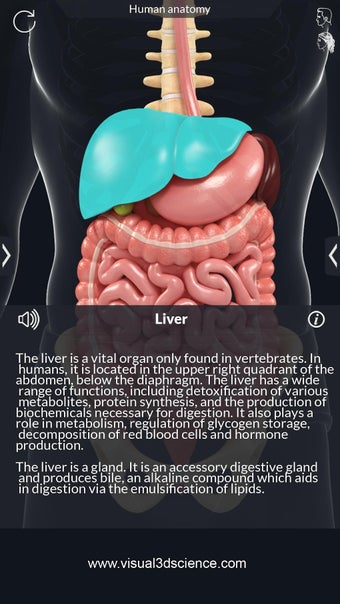

La interfaz fácil de usar de My Organs Anatomy permite una navegación sencilla, lo que facilita la selección, rayos X, ocultación y visualización de órganos individuales. La aplicación también incluye un modo de animación, opciones de búsqueda y un panel de información que proporciona información relacionada. Además, la aplicación ofrece pronunciación de audio para todos los términos anatómicos, e incluso los usuarios pueden dibujar o escribir en la pantalla y compartir capturas de pantalla.

En general, My Organs Anatomy es una gran aplicación para estudiantes de medicina y cualquier persona que quiera explorar la anatomía de los órganos humanos en detalle. Con sus gráficos de alta calidad y numerosas características, esta aplicación proporciona una excelente experiencia de aprendizaje para los usuarios.